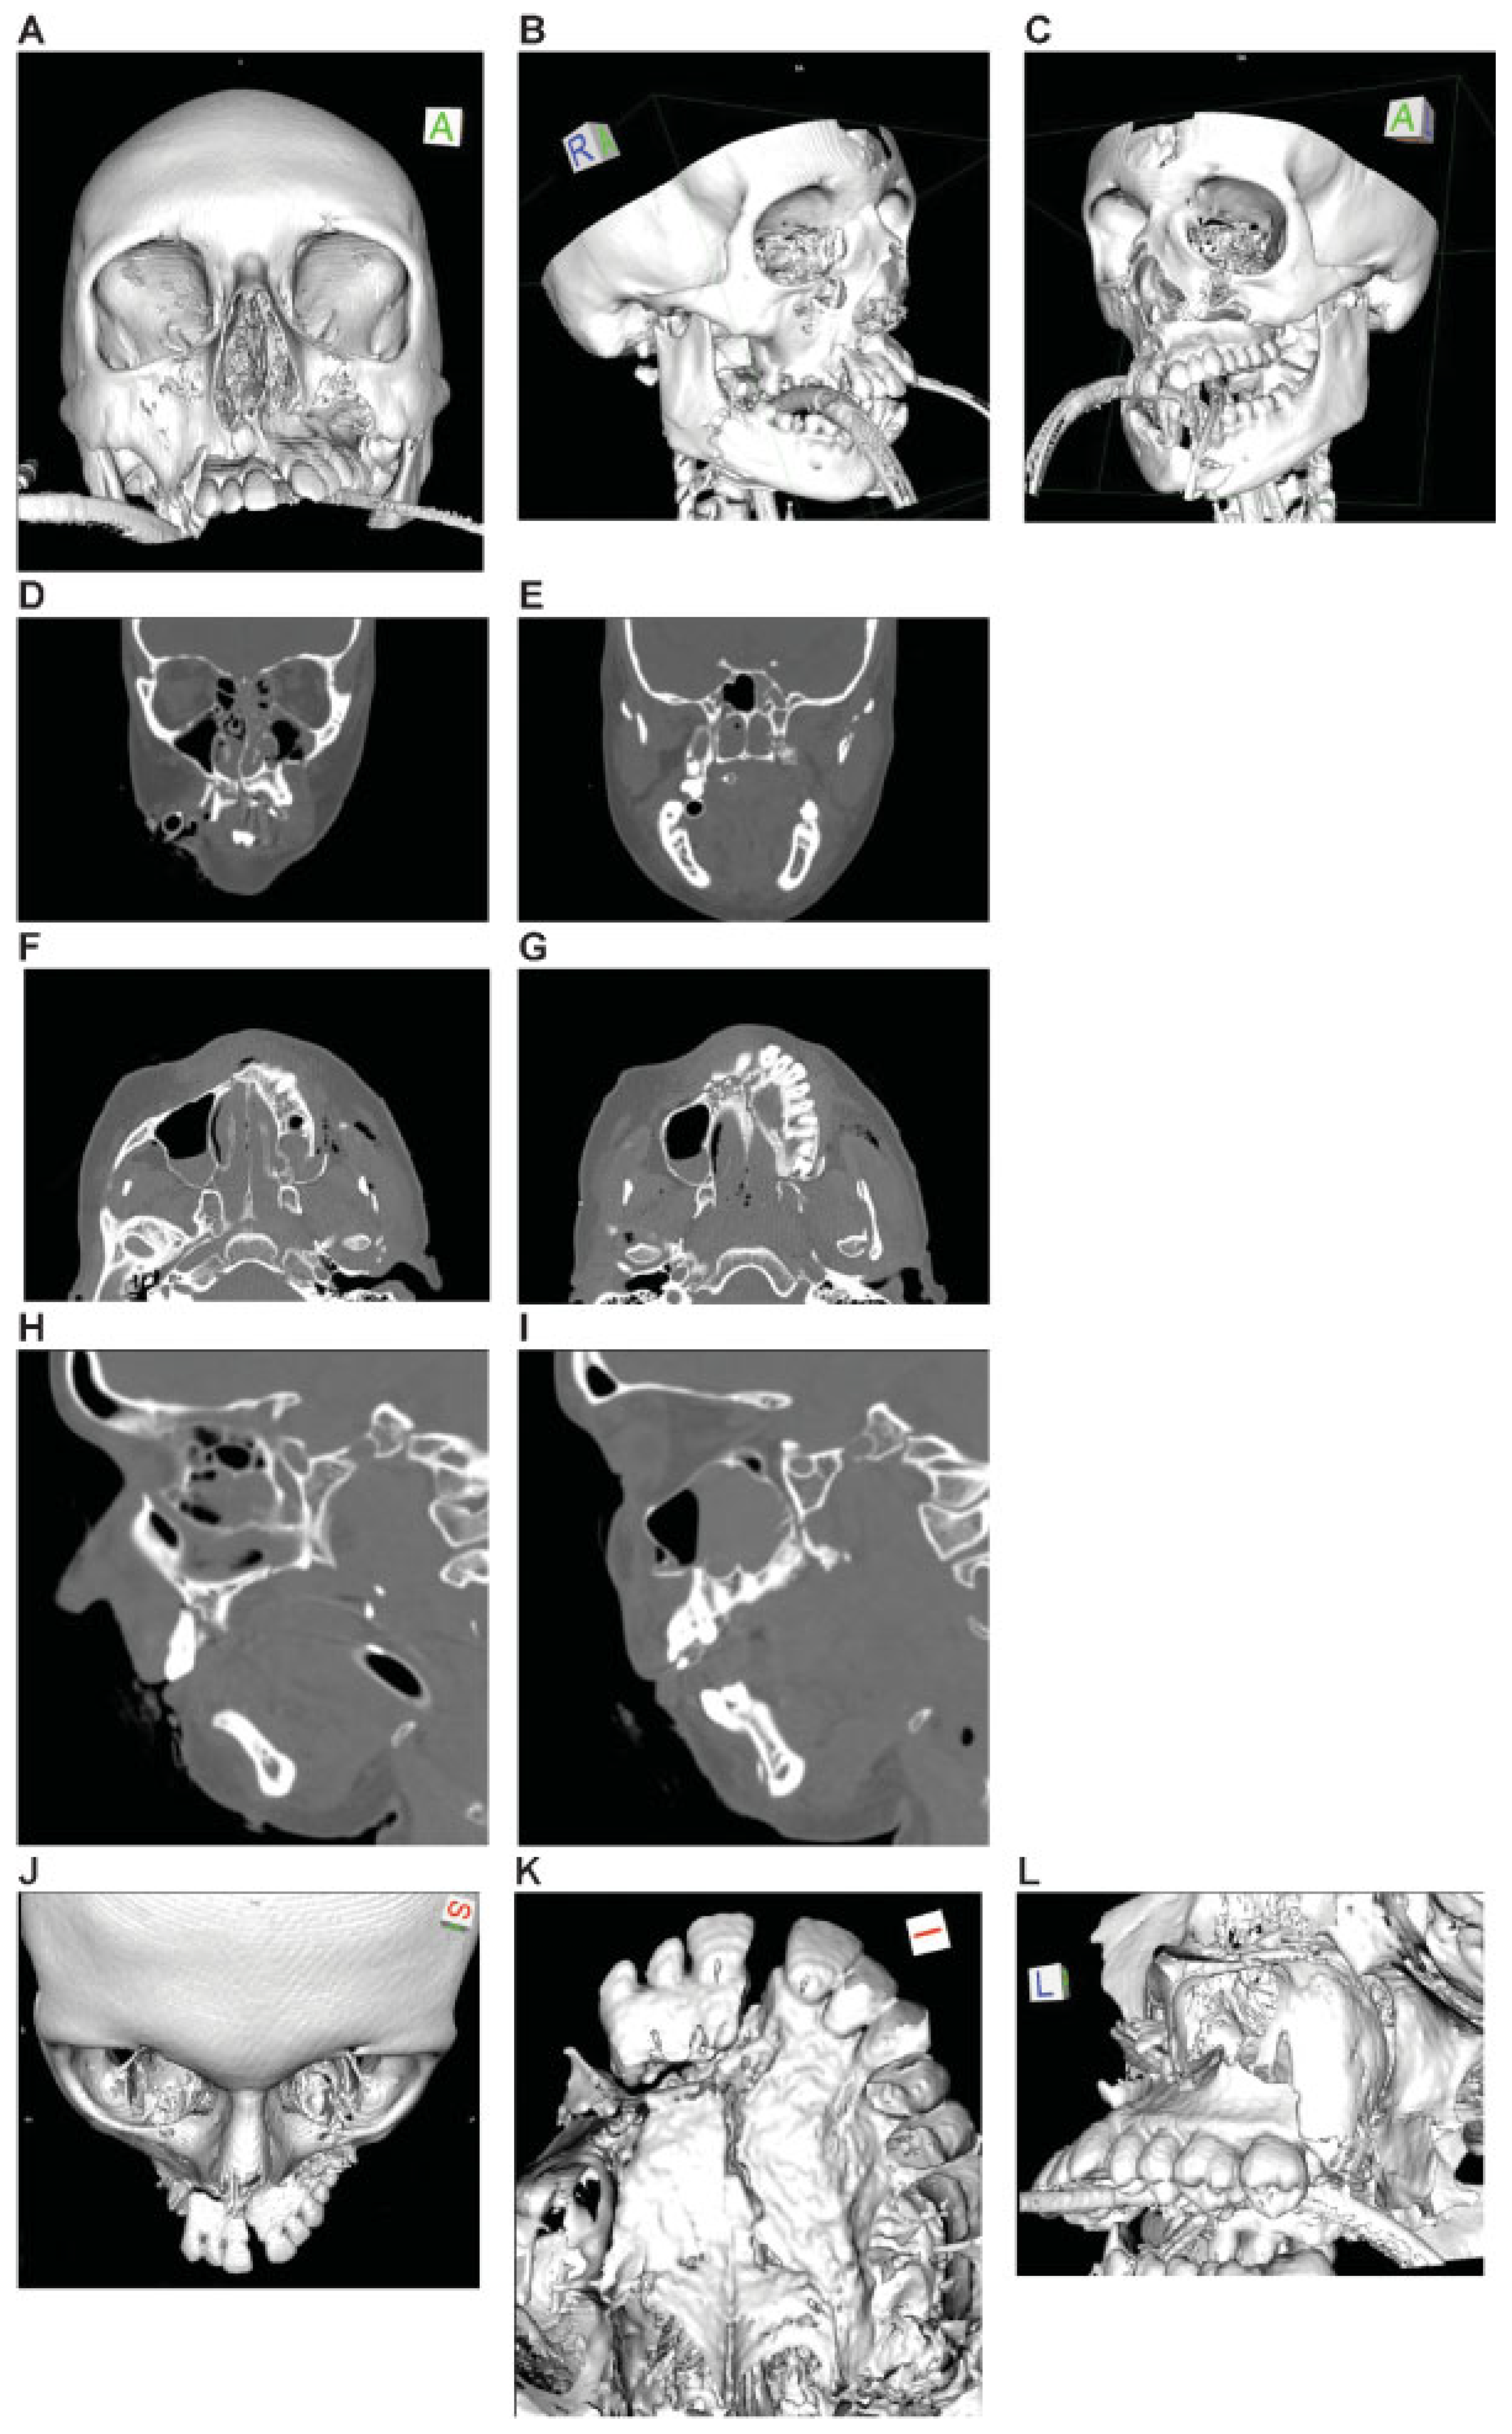

Figure 11.

Panfacial fracture including lower central midface fracture analogous to Hemi Le Fort I fracture. Imaging: Three-dimensional (3D) computed tomographic (CT) scans—(A) frontal view, (B) oblique lateral view right, (C) oblique lateral view left, (D, E) coronal CT scans; (F, G) axial CT scans; (H, I) sagittal CT scans; 3D CT scan details—(J) superofrontal view, (K) palatal from below, (l) pterygomaxillary junction. Narrative description: Midface component of panfacial fracture: LCM fracture left, paramedian midline fracture of the palate; left maxillary alveolar process fracture 11–13, vertical tooth fracture 14, avulsion 15. Details: Dentition (FDI) preinjury: completely dentate. Palate: Paramedian fracture left. Pterygoids: No involvement. Displacement: Anterosuperior displacement of the LCM fragment left, multifragmentation of the antral wall left, Infraorbital rim left intact. Internal orbits: No involvement. (M) Level 3 Code : 91 P.A.S.P - 92 La.P2.L1. This case example CMTR-92-103 is made available electronically for viewing using the AOCOIAC software at www.aocmf.org/classification. Mandible component according to level 2: four fracture regions: condylar process bilaterally, right angle/ramus and symphyseal region. Mandible component according to level 2: four fracture regions: condylar process bilaterally, right angle/ramus and symphyseal region.